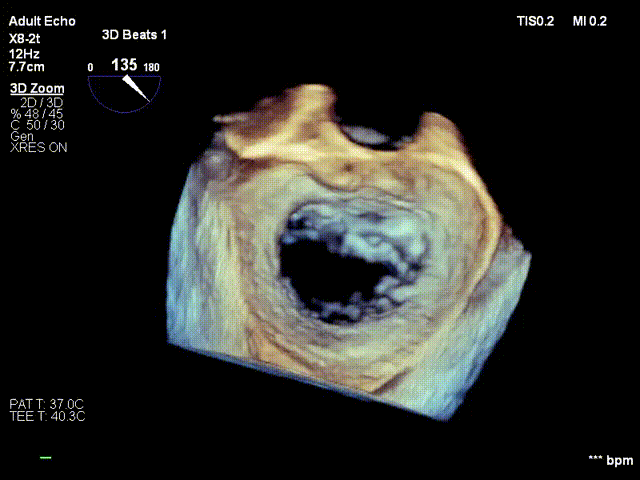

术前3D

前后瓣叶均可见栓系

反流主要来源于2区累及1、3区